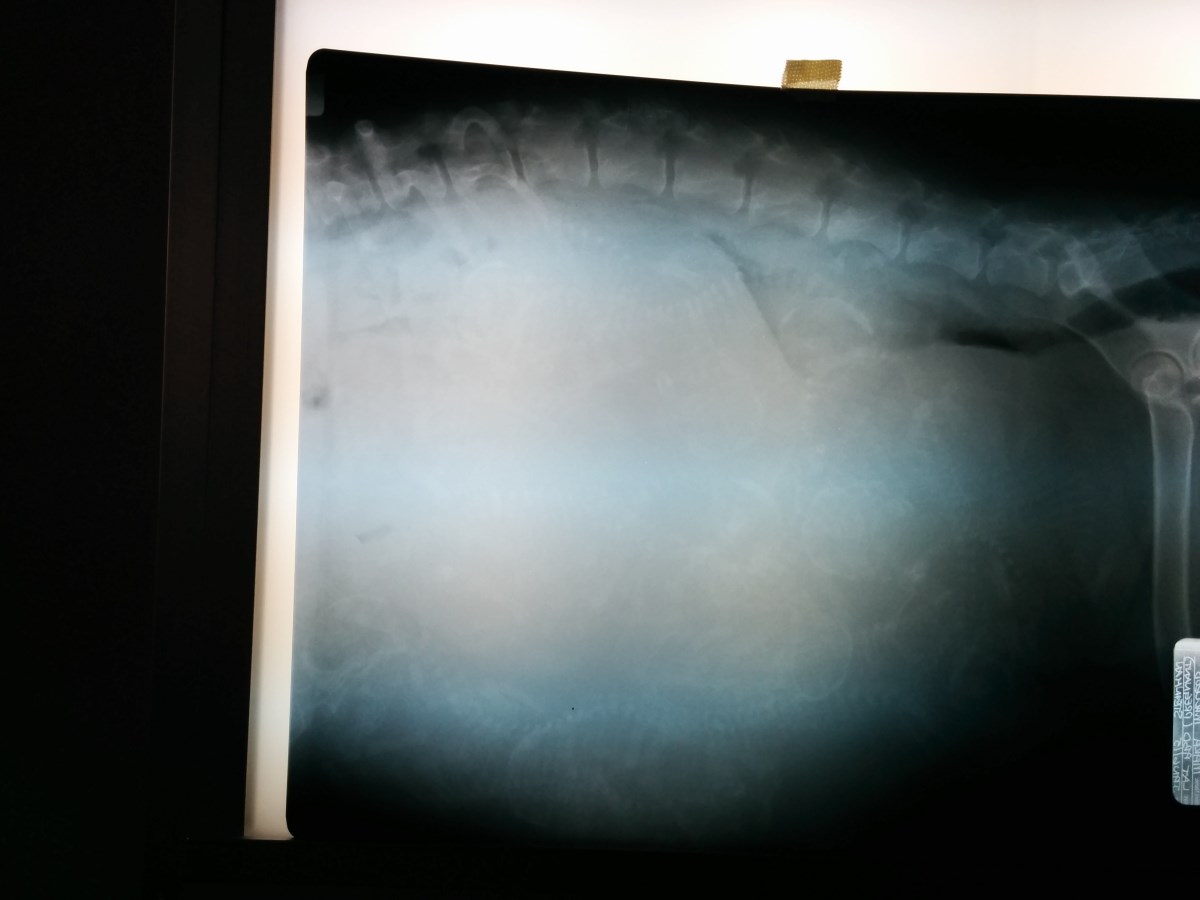

Enlargement of Mara's x-ray showing many puppy skeletons.